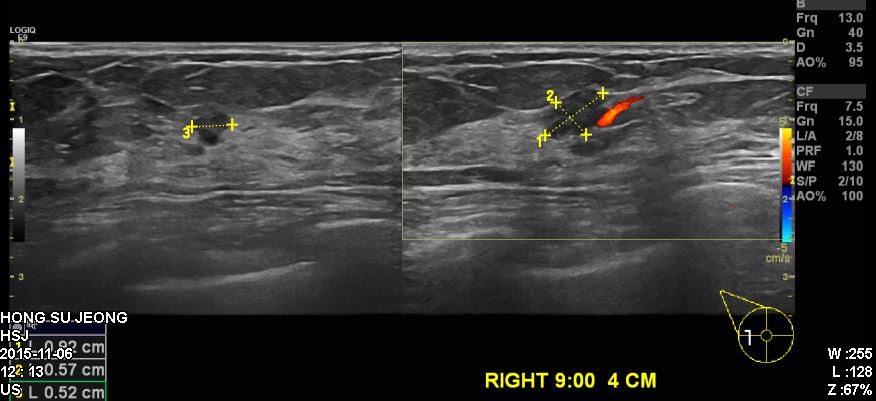

건진상 이상소견으로 내원하신 60대 환자분이십니다.

본원서 우측유방에 혹 조직검사 시행하였고

결과상 침윤성 유관암 진단되었습니다.